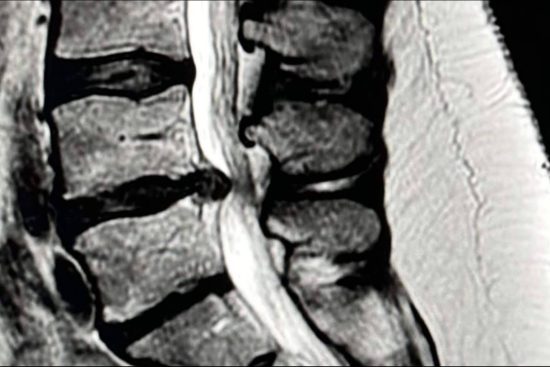

Cuando una hernia discal lumbar provoca dolor en la pierna (ciática), lo primero es intentar un tratamiento conservador: reposo relativo, medicación, fisioterapia o infiltraciones. En la mayoría de casos, estos tratamientos funcionan, pero si el dolor persiste tras unas 6–8 semanas, si aparecen síntomas neurológicos que empeoran (como pérdida de fuerza o sensibilidad) o un síndrome de cola de caballo (pérdida de control de esfínteres), puede ser necesario recurrir a la cirugía.

La microdiscectomía es la técnica de referencia desde hace años. Consiste en retirar el fragmento del disco que comprime el nervio a través de una pequeña incisión en la espalda. Es una cirugía muy segura, eficaz y con resultados predecibles a largo plazo. Una de sus grandes ventajas es que sirve para la mayoría de tipos de hernias discales y los cirujanos tienen una amplia experiencia en ella. La parte menos favorable es que, aunque se considera mínimamente invasiva, implica una mayor manipulación de los músculos de la espalda que otras técnicas más modernas.

La discectomía endoscópica es más reciente y se realiza introduciendo una cámara a través de pequeñas incisiones. Esto nos permite trabajar con mínima agresión sobre los tejidos y visualizar la cirugía en una pantalla. Los resultados en cuanto a alivio del dolor y recuperación funcional son iguales a los de la microdiscectomía, pero con algunas ventajas: menos sangrado, menos dolor después de la intervención, cicatrices más pequeñas y una recuperación más rápida. El inconveniente es que requiere una curva de aprendizaje mayor y, en algunos casos, la cirugía puede durar algo más.